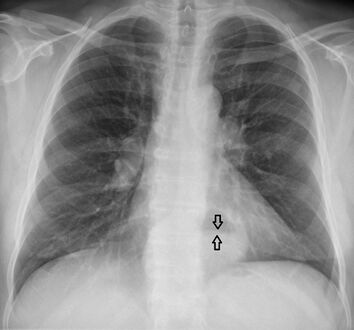

-

فتق حجابي كبير في صورة للصدر بالأشعة السينية، حيث يُميز بأسهم مفتوحة على النقيض من حدود القلب التي تتميز بأسهم مغلقة.